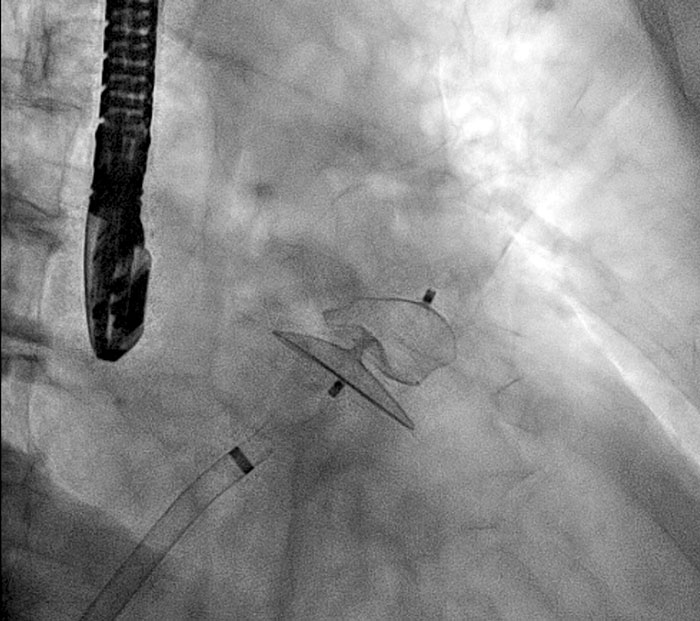

Figur 1a. Alivecore I-ECG, exempel på enkel metod för förmaksflimmerscreening.

Figur 1b. MyDiagnostick, exempel på enkel metod för förmaksflimmerscreening.

Figur 1c. Zenicor tum-EKG, exempel på enkel metod för förmaksflimmerscreening.

Utöver pulspalpation har man i andra studier använt olika metoder för att hitta förmaksflimmer, som enstaka 12-avlednings-EKG. I en metaanalys bestämdes förekomsten av tidigare okänt förmaksflimmer till 1,4 procent med hjälp av enstaka 12-avlednings-EKG i åldern över 65 år [13]. Nackdelen med denna metod är att man framför allt hittar individer med permanent arytmi, och inte de individer som har ett paroxysmalt förmaksflimmer. Andra tänkbara metoder för att hitta förmaksflimmer är långtidsregistreringar av hjärtrytmen med bandspelar-EKG eller olika metoder med möjlighet för patienter att själva spela in hjärtrytmen (så kallade event recorders eller händelse-EKG). I Australien har man genomfört en studie där man använt en särskilt anpassad Iphone (Figur 1a) för att registrera hjärtrytmen hos 1 000 apotekskunder > 65 år och hittat okänt förmaksflimmer hos 1,5 procent [14]. På influensakliniker har 676 patienter med medelåldern 74 år provat en handhållen EKG-utrustning kallad MyDiagnostick (Figur 1b), och man fann då tidigare okänt förmaksflimmer hos 1,6 procent [15]. I Sverige har just inklusionen i en stor systematisk screeningstudie för förmaksflimmer hos 75/­76­­­­­-åringar som heter STROKESTOP avslutats. Den bygger på en pilotstudie genomförd i Halmstad där man med hjälp av stegvis screening för förmaksflimmer hos 75-åringar hittade 7,4 procent nya förmaksflimmer [16]. I STROKESTOP-studien har man randomiserat alla 75/76-åringar bosatta i Stockholm och Halland i ett 1:1-förfarande att delta i screening för förmaksflimmer eller att medverka i en kontrollgrupp. I denna studie har en enkel handhållen EKG-utrustning (www.Zenicor.com) (Figur 1c) lånats ut till deltagarna, som med hjälp av mobilteknologi skickat 30 sekunders-EKG i en avledning 2 gånger/dag under 14 dagar [17]. Avsikten med denna metod var att försöka detektera fler paroxysmala förmaksflimmer. Nypublicerade data visar att 3 procent av 7 173 deltagare har nyupptäckt förmaksflimmer och att > 90 procent av deltagare med nyupptäckt förmaksflimmer accepterar initiering av antikoagulantiabehandling [18]. Tandvårds- och läkemedelsförmånsverket (TLV) har i ett kunskapsunderlag gjort en hälsoekonomisk utvärdering av tum-EKG-screening i den äldre befolkningen och befunnit denna kostnadseffektiv [19]. Nyare metoder för förmaksflimmerscreening sammanfattas i Tabell I.